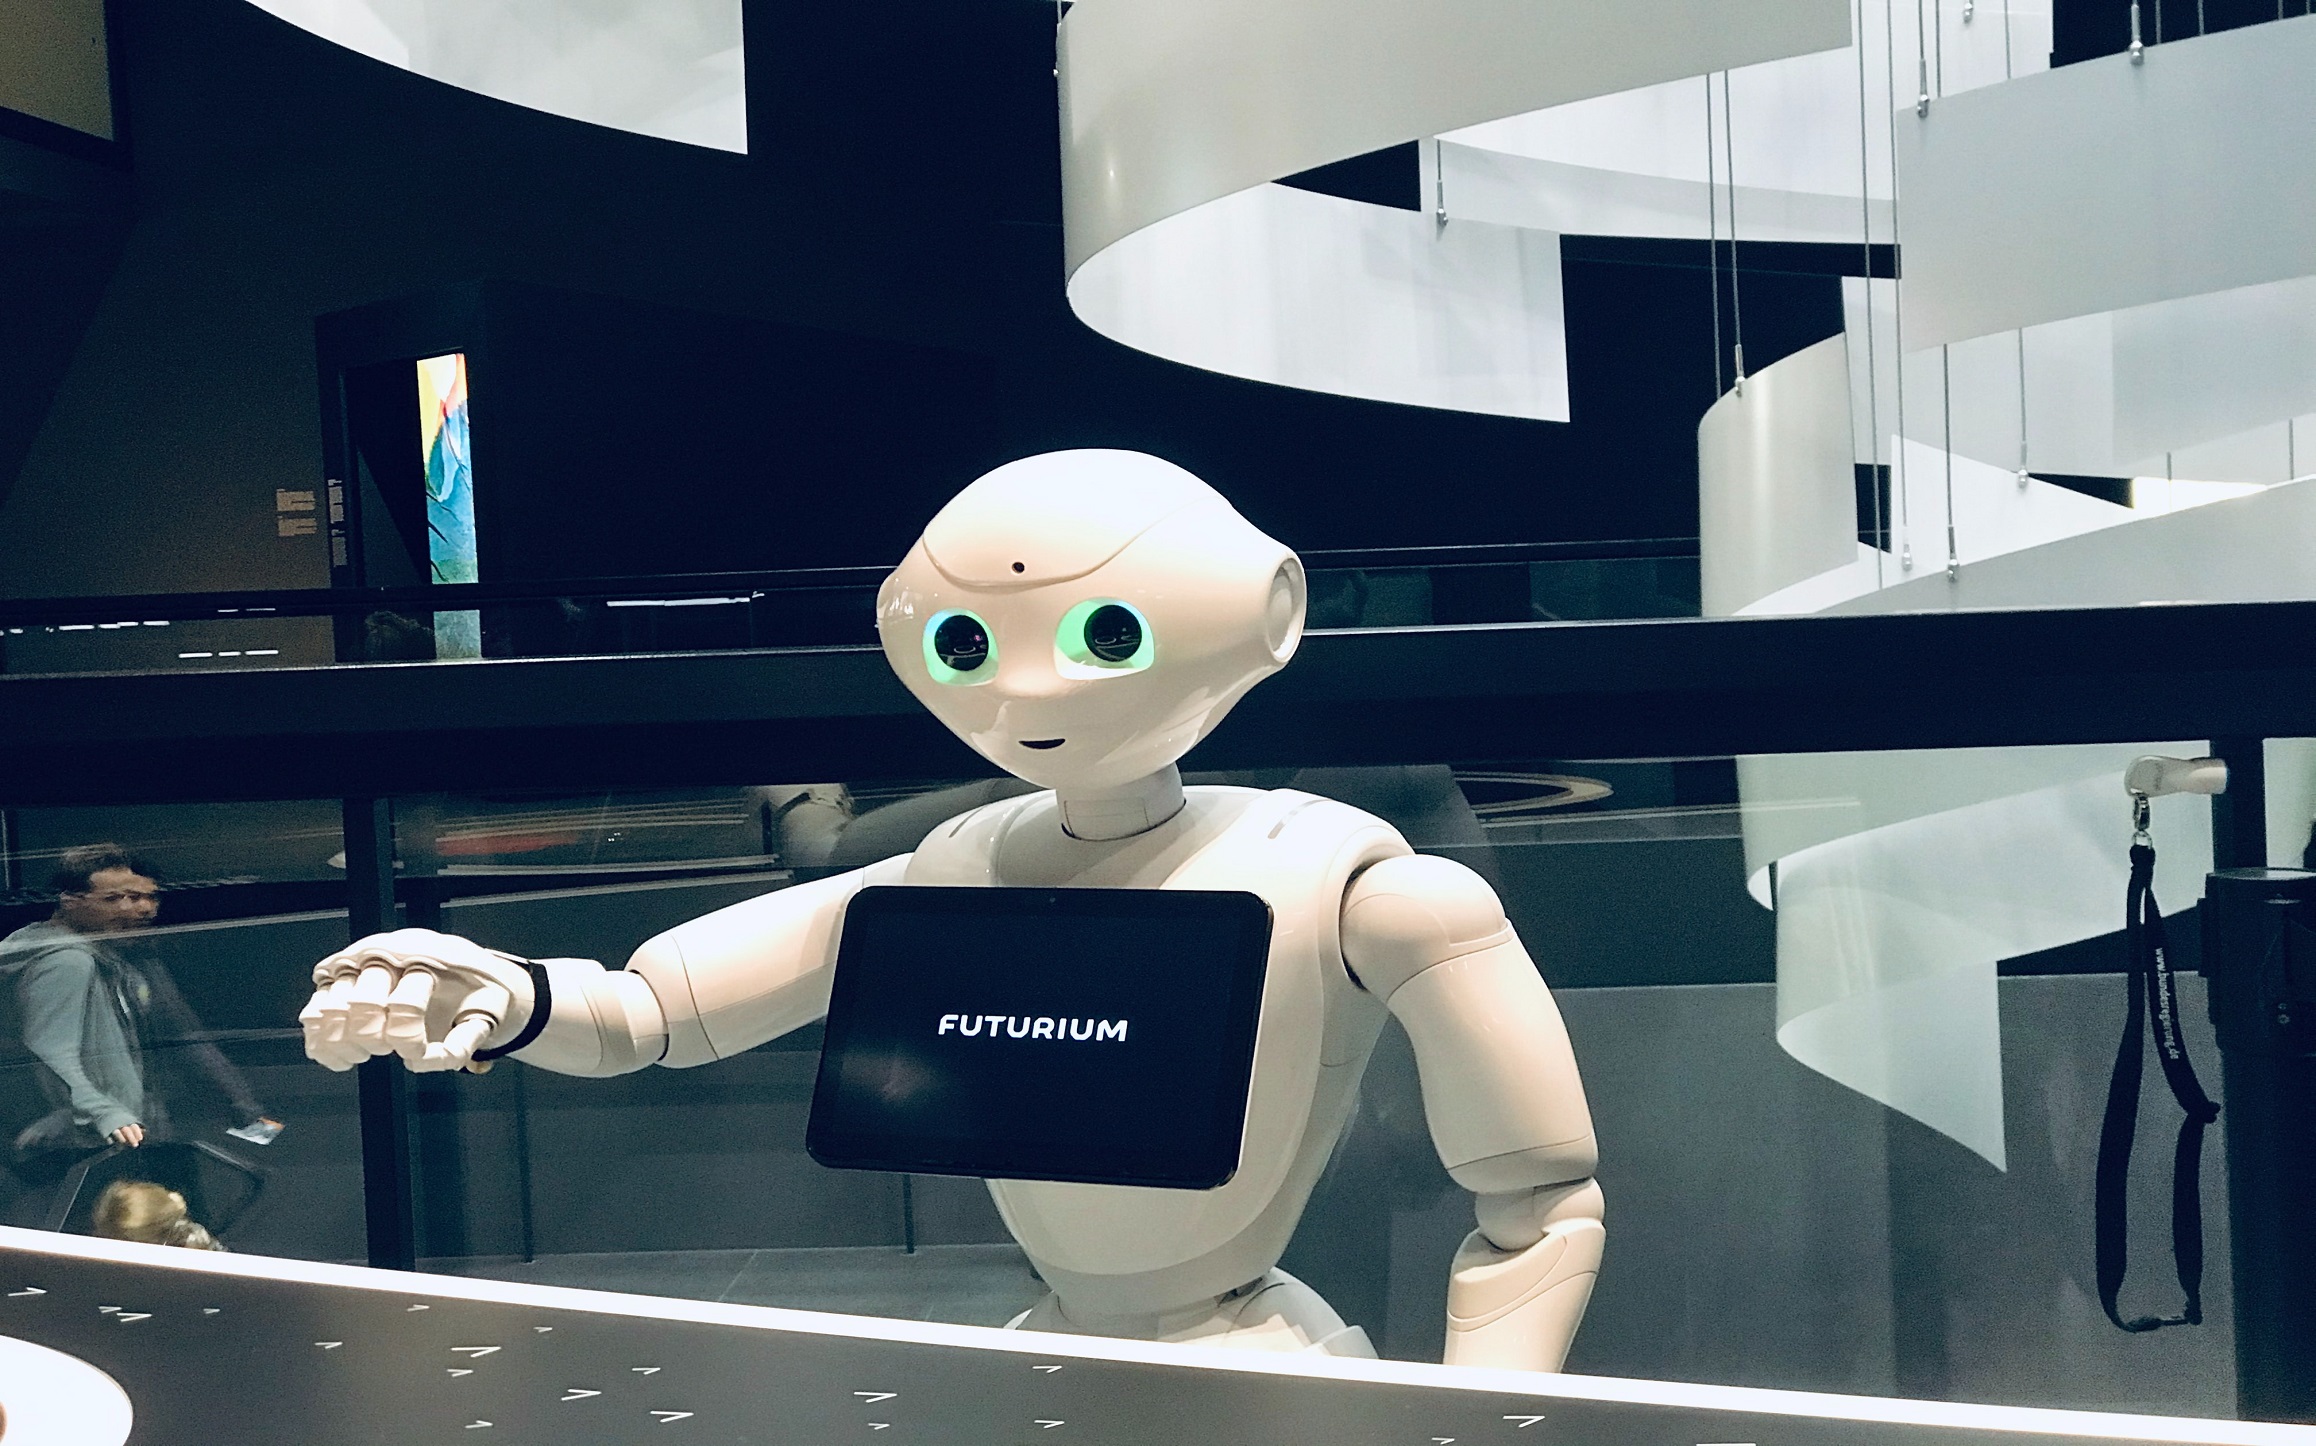

Robot Assisted Kidney Transplant in France

Open kidney transplant is an established procedure, considered the best treatment for end stage renal failure. However, it carries all the disadvantages of open surgeries. Wound...

- By Dr. Anant Kumar

- December 31, 2020